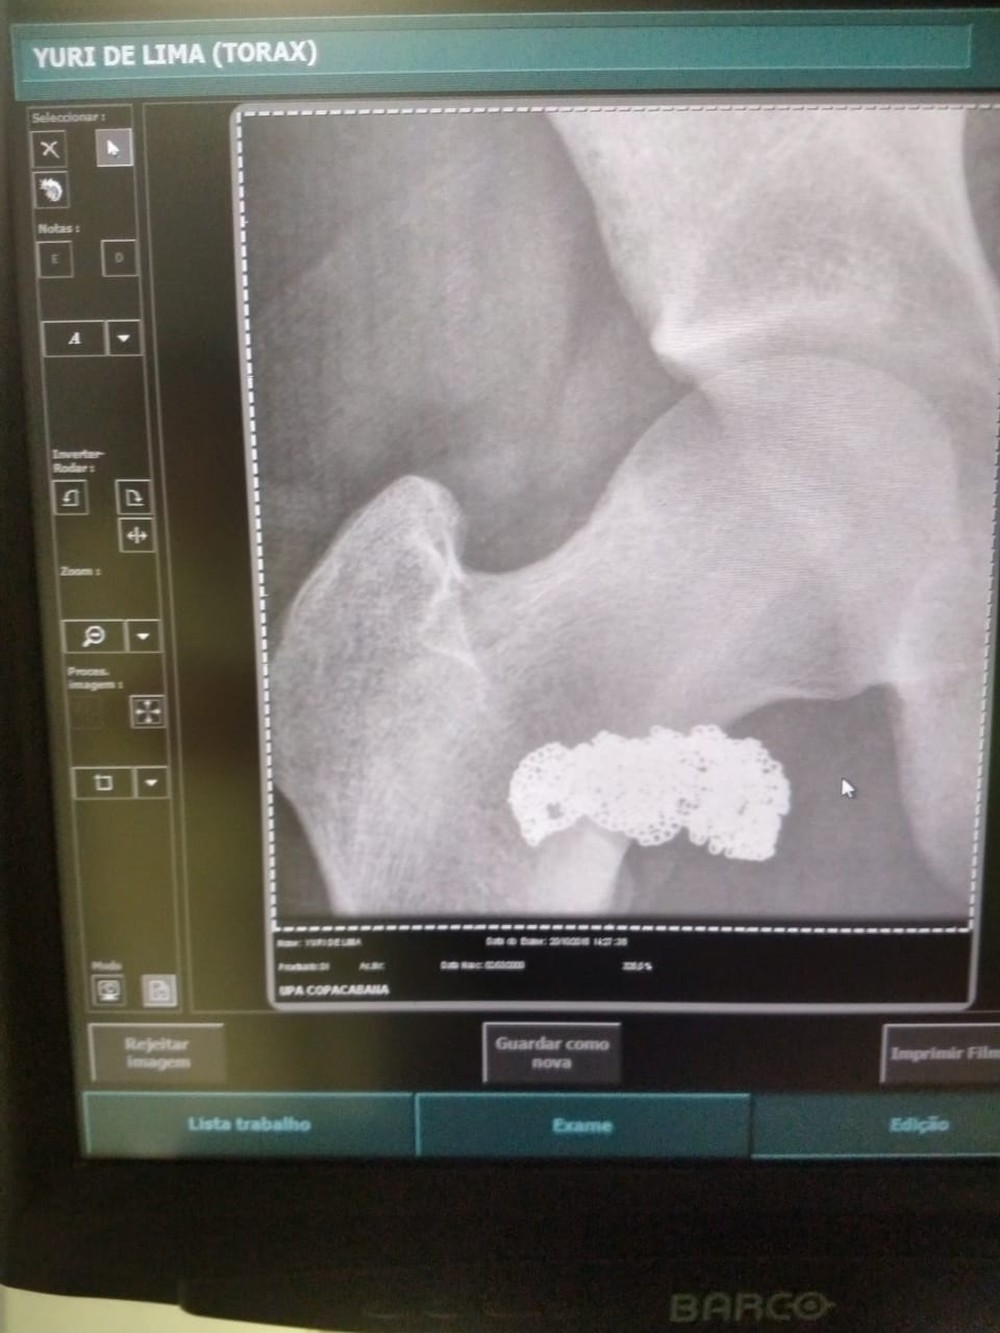

Ele engoliu a joia e se disse inocente, mas foi preso depois que o exame de raio-x constatar que o cordão estava no abdômen dele.

A polícia decidiu levar o autor do roubo para um exame na UPA de Copacabana onde a ressonância mostrou uma mancha, próxima do seu abdômen. Com o zoom, ficou claro que era o cordão.